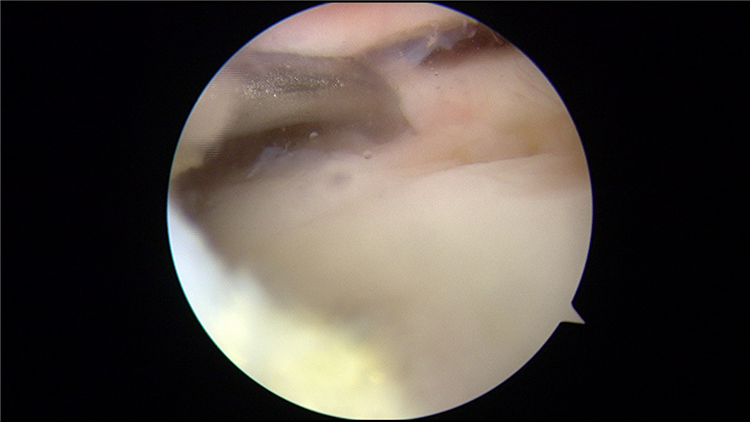

踝关节镜下的病灶局部踝关节镜下骨髓刺激术